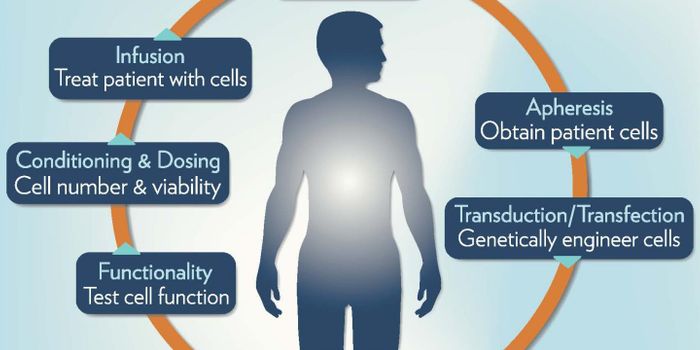

AUG 31, 2017CancerFor patients battling leukemia, there is hope in the form of a newly approved gene therapy. Called Kymriah, this is the ...